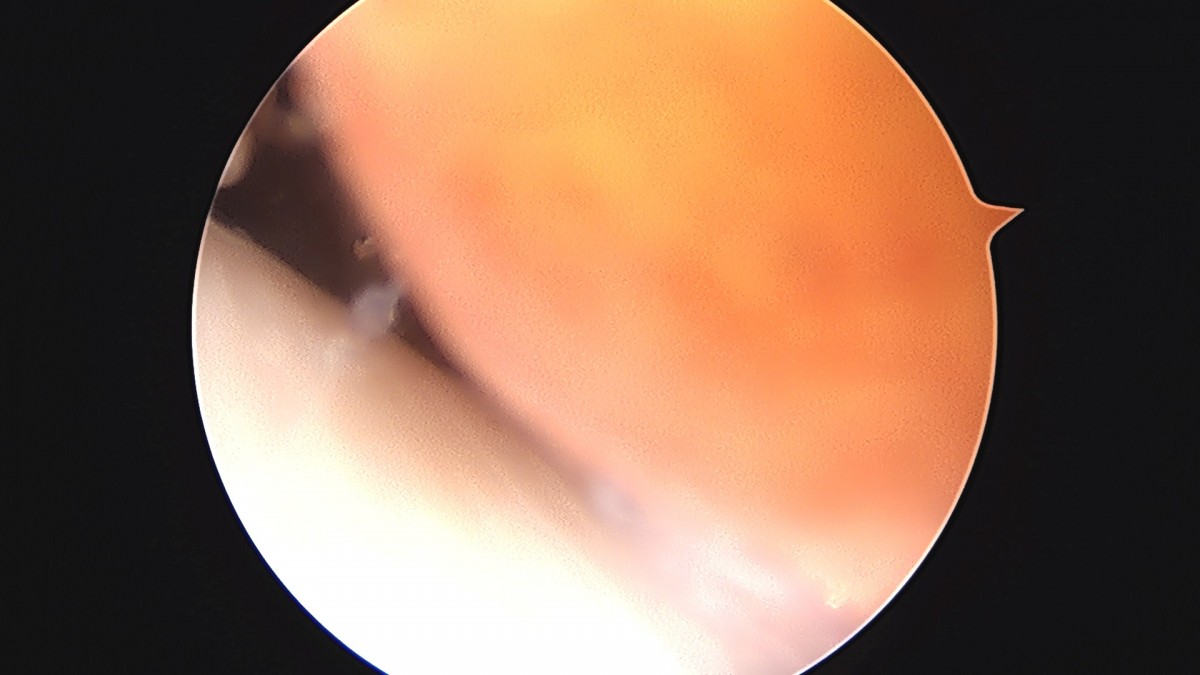

이재상원장님 무릎 반월상 연골판 절제술 강일O 환자

dae765e4d9ac96aee867c9d6292d8784_1758006723_7513.jpg